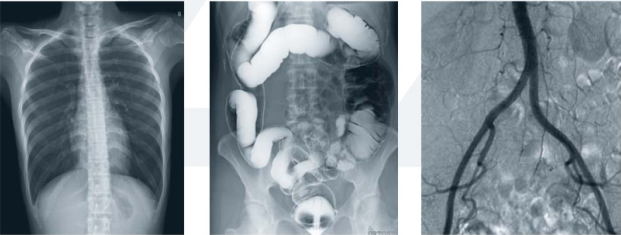

動態(tài)DR擁有可視化造影功能,在進行造影檢查時,成像幅面大,無需移動球管,一個幅面就可以連續(xù)觀看造影劑的流向以及造影部位的全部情況,在造影過程中還能實現(xiàn)900萬像素實時點片,為醫(yī)生的臨床診斷提供優(yōu)異的影像數(shù)據(jù)。

動態(tài)DR能實現(xiàn)全身拼接,適用于全脊柱、全下肢攝影,輔助脊柱畸形的矯形治療、康復檢查,為臨床提供高精度圖像。

動態(tài)平板DR的透視和攝影均使用同一高效動態(tài)平板,提供無與倫比的臨床應用范圍,包括幾乎所有的普放檢查、胃腸鋇餐檢查和血管造影檢查等。